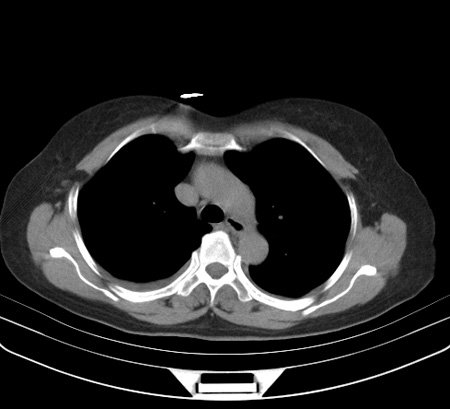

以下是引用余辉在2009-2-19 20:10:00的发言:[br]多考虑急性感染性病变,右中叶尚可见多枚小斑片状影,多为化脓性肺炎,双侧胸腔积液

以下是引用随光逐影在2009-2-19 20:33:00的发言:[br]1)考虑右肺炎症;建议抗炎治疗后复查。2)双侧胸腔积液(以右侧为甚)。

以下是引用花凤凰在2009-2-19 20:46:00的发言:[br]病人有发热,胸痛急性起病,主要病变位于右肺中叶外侧段,呈楔行改变,位于外带胸膜下,考虑为肺梗塞可能!!!!!!!!!!!!!!!!!!!!!!!!!!!!!!!!!!!